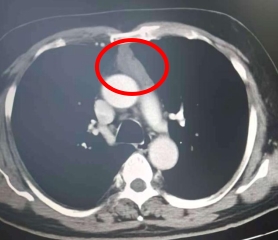

60岁的李先生(化名)近两年来深受胸闷、胸痛症状困扰,有时还出现呼吸气喘的情况,严重影响生活质量。两个月前,他慕名来到我院就诊,经胸部CT等详细检查后,被确诊为前纵隔肿瘤,肿瘤大小约51*19毫米。更棘手的是,该肿瘤位置较深,前方被胸骨遮挡,后方紧邻心脏、大血管等重要器官,手术操作空间狭窄,稍有不慎便可能引发严重并发症,手术难度极大。

术前CT显示前纵隔肿瘤